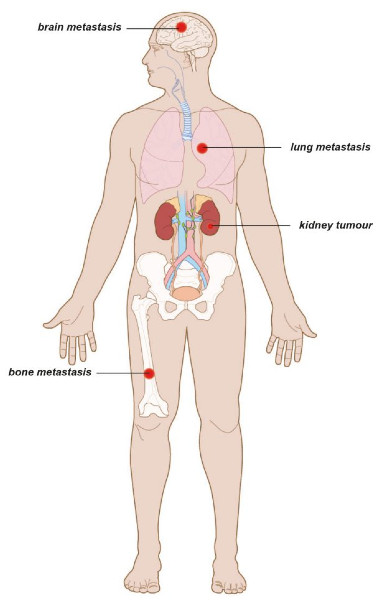

Θεραπεία του μεταστατικού καρκίνου του νεφρού

Ο καρκίνος του νεφρού μπορεί να εξαπλωθεί σε άλλα όργανα ή σε απομακρυσμένους λεμφαδένες (Εικ. 7). Αυτό ονομάζεται μεταστατική νόσος. Στη μεταστατική νόσο, ο όγκος του νεφρού αναφέρεται ως πρωτοπαθής, ενώ οι όγκοι σε άλλα όργανα ονομάζονται μεταστάσεις.

Εικ. 7: Ο μεταστατικός καρκίνος του νεφρού μπορεί να εξαπλωθεί στους πνεύμονες, τα οστά ή τον εγκέφαλο